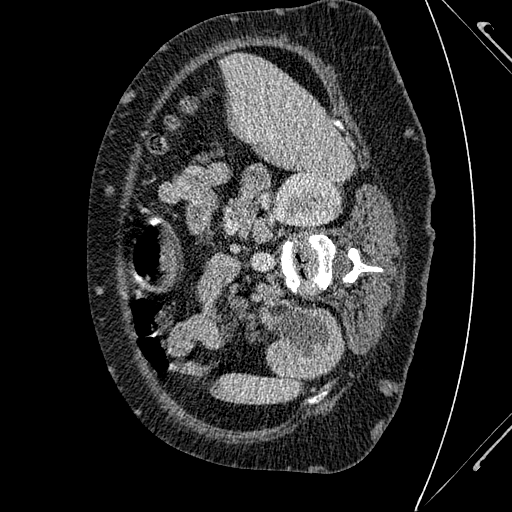

This challenge includes liver segmentation and liver tumor segmentation. The dataset consists of 131 training datasets and 70 testing datasets, all of which are 3D abdominal CT scan images that contain liver. Label maps (annotations) are provided for the training data, but not for the testing data. Participants are required to train their model on the training data, then use the well-trained model to make predictions for the testing data. The prediction can be submitted back to the orgnizer for blind evaluation. An example 3D CT data visualized in different directions is shown in Figure 5.

Refer to caption

Figure 5: Different positions of an example 3D CT data. Upper left: oblique coronal position. Upper right: add annotation (label) to the upper left image, where yellow area is the liver, green areas are the tumors on the liver. Lower left: sagittalia position; lower right: oblique-axial position.